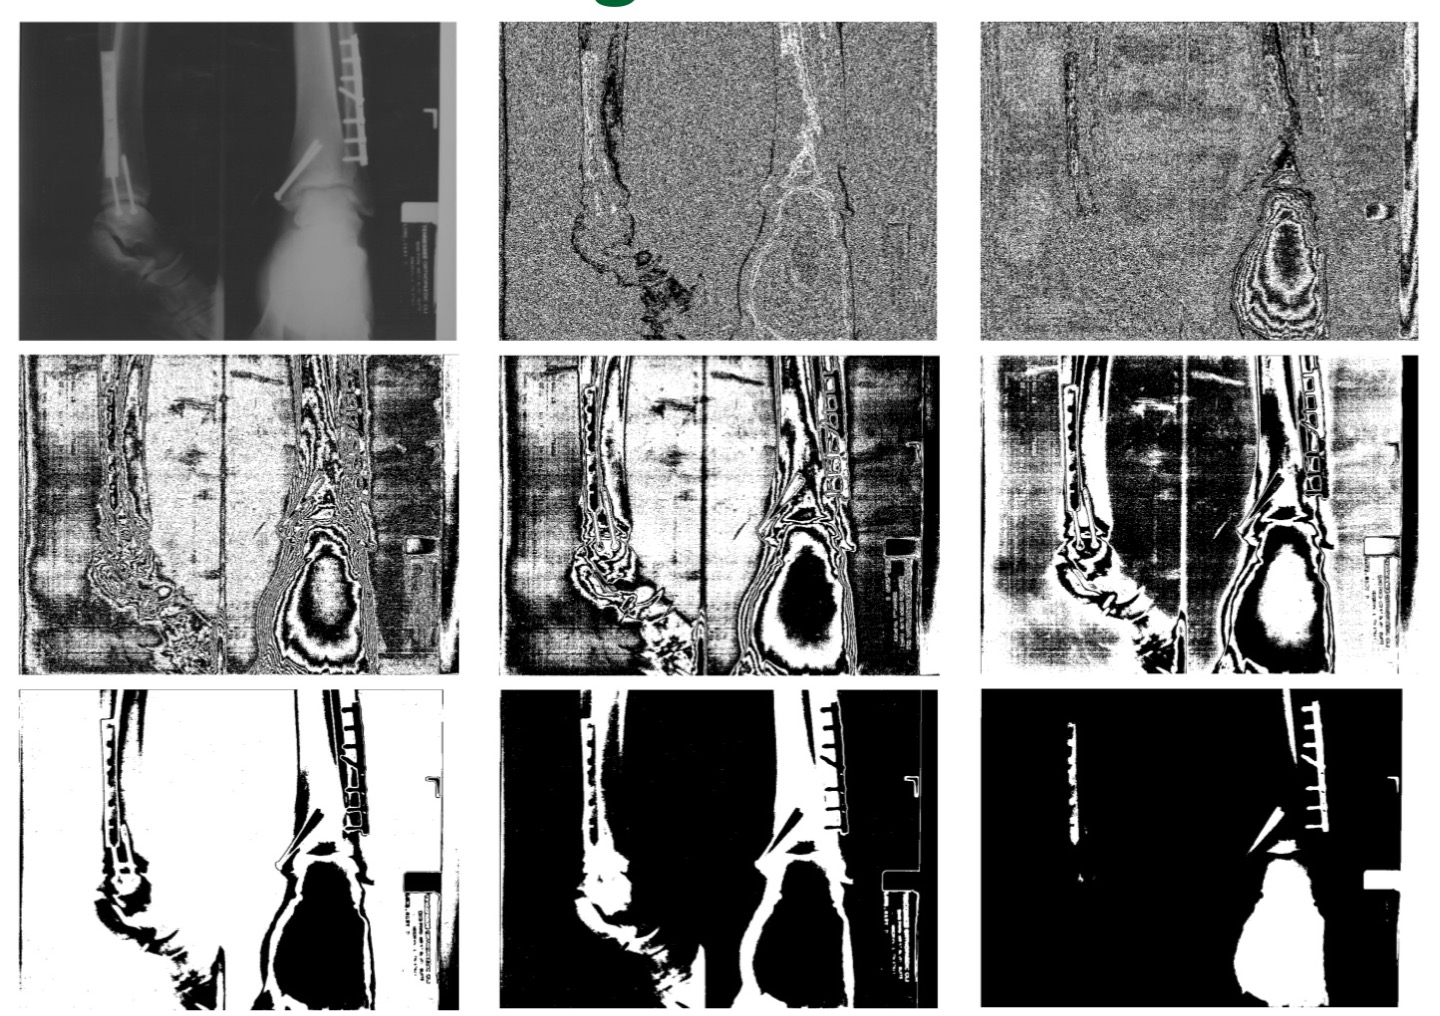

Bit-Plane Slicing

Bit-Plane Slicing은 이미지의 각 픽셀 값을 이진수로 표현했을 때의 각 비트 수준(Plane)을 분리하여 분석하거나 처리하는 영상 처리 방법이다.

이전에 Grayscale Pixel Value는 0~255의 범위를 가지는 8bits이다. 따라서 한 픽셀의 픽셀값은 8개의 2진수로 나타낼 수 있다. 따라서 전체 이미지에 대하여 각 픽셀을 비트 수준(Plane)에 대하여 0,1인지 구분하고, 1이라면 해당 Plane에 255를 나타내고 0이라면 0을 나타내는 방법이다.

$2^7$을 나타내는 비트 Plane을 보자. 255에 가까운 즉, 흰색에 가까울수록 해당 픽셀 값은 128을 넘길 것이다. 따라서 해당 비트 자리에는 1이다. 하지만 어두운 값은 해당 비트자리에는 0이 들어갈 것이다. 이처럼 극단적인 색상 비교를 하거나, 각 비트 수준으로 분리하여 처리할 때 이와 같은 방식을 사용한다.